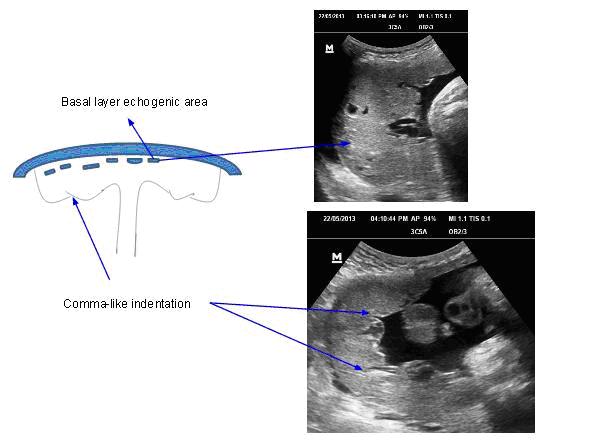

Grade - 2

Notable changes in all the three layers

Chorionic plate - more marked indentations as compared to the grade 1

Placental substance - incompletely divided by the appearance of linear ( comma ) echogenic densities / line.

Basal layer - linear small echoes are arranged with their long axis parallel to the basal layer. Larger calcifications in a "dot-dash" configuration along the basilar plate ( basal stippling )

Basal echoes in the placenta are a hallmark of a grade ll placenta